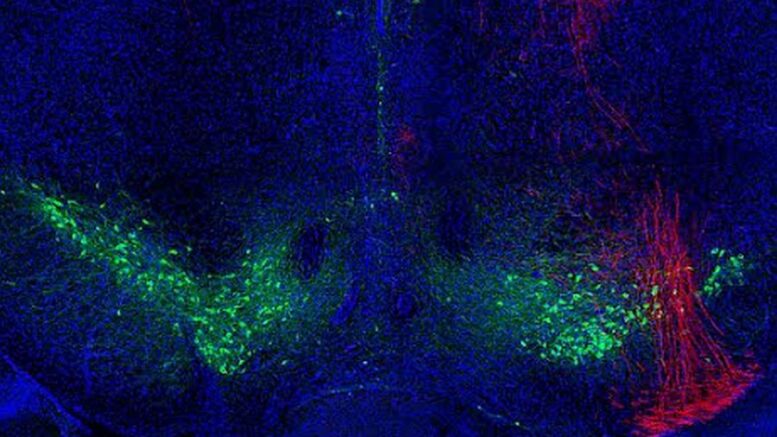

The loss of neurons (brain-based nerve cells) and dopamine (brain-based neurotransmitters) has been well-documented by scientists studying the dreaded nervous-system disorder. But exactly how this “dopaminergic modulation” affects motor skills is unclear, prompting researchers in the Renaissance School of Medicine’s Department of Neurobiology and Behavior to consult an experimental model, designed to mimic a motor cortex in decline.

But the three-part experimental model – which pharmacologically blocked carefully selected motor-cortex receptors, then poisoned dopaminergic neurons in the midbrain (to mess with the basal ganglia), then killed off dopamine neuron axons (itty bitty intra-neuron connectors) in the motor cortex – shed new light on precisely how the dopamine decline affects the motor cortex’s input/output functions.